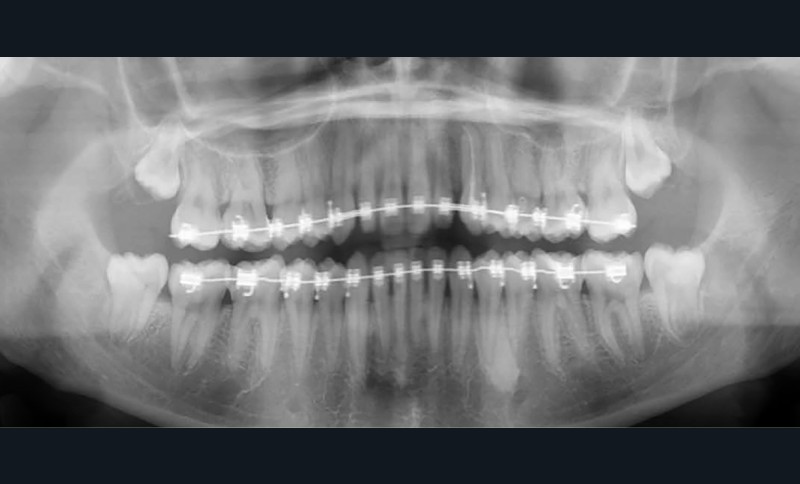

La radiographie panoramique permet de confirmer l’inclusion de la 23, apicale aux dents 21 et 22, ainsi que la présence d’un odontome en apical de la 63. Ces éléments nécessitent la réalisation d’un CBCT.

Le CBCT révèle une position très apicale de la 23. L’apex est fermé.

Diagnostic (fig. 1 et 2)